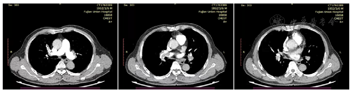

CT肺动脉造影示双肺动脉主干末端及分支栓塞;双肺多发斑片、条片及结节影,考虑炎症;右肺中叶小钙化灶。超声心动图示Lved 37.8 mm,Ef 61.2%(Teich),三尖瓣中度反流,估测肺动脉收缩压73 mmHg,室间隔增厚,主动脉瓣钙化。下肢静脉彩超示右侧股浅静脉下段、腘静脉、胫后静脉实体回声(血栓?)。心电图示窦性心动过速,T波改变。

患者,男性,70岁,已婚。主诉:腓骨骨折8 d,气促1 d余,加重14 h。患者8 d前因右侧腓骨骨折就诊当地医院,行"石膏固定术"后卧病在床,期间无胸痛、气促,无咳嗽、咯血,无心悸、晕厥不适。1 d余前(2022年4月10日13:00)突发气促,活动后加重,休息症状减轻,起初未重视,未诊治。14 h前上述症状加重,伴濒死感,无胸痛、咳嗽、咯血、晕厥不适,遂急诊我院,查D-二聚体10.43 μg/ml;CT肺动脉造影示双肺动脉主干末端及分支栓塞;超声心动图示三尖瓣中度反流,估测肺动脉收缩压73 mmHg(1 mmHg=0.133 kPa);下肢静脉彩超示右侧股浅静脉下段、腘静脉、胫后静脉实体回声(血栓?)。考虑"急性肺动脉栓塞",予低分子肝素钠抗凝、平喘、抗感染等处理后,拟"急性肺栓塞"收住心内科CCU病房。